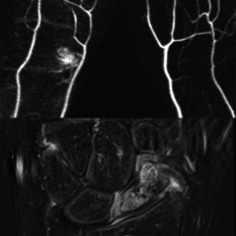

Methods: This was a prospective study. Between 2022 and 2023, contrast-enhanced magnetic resonance angiography and gadolinium-enhanced magnetic resonance imaging were performed in 32 patients (28 males and 4 females) with scaphoid fractures. The average age was 35 years (ranges: 15-74 years). We observed the accumulation and filling time of contrast media, and measured the diameters of extraosseous arteries as well as the signal intensity of intraosseous perfusion. The Mann-Whitney U-test, student's t-test, and Friedman test were used, respectively.

Results: 31 of 32 patients showed contrast media accumulation in the wrist joints on the affected sides. The filling time of contrast media on the affected sides was 5.6 (6.05-1) s quicker than on the healthy sides. The diameters of the radial arteries on the affected side increased by 12.8% (SD, 18.4%) compared to those on the healthy side (p = 0.002). All the patients had visible scaphoid nutrient arteries originating from the radial arteries on the affected side. The number of visible arteries on the healthy side was lower. Blood supply to the scaphoid was not related to the patient's sex, injury side, or fracture site. The increase in blood supply at the proximal fragment in older patients was less than that in young individuals (p = 0.015). Blood supply to the proximal and distal fragments of the scaphoid increased after fracture (p < 0.05). Within 1 month after the fracture, the increase in blood supply at the proximal fragment was less than that at the distal fragment, and it increased significantly after 1 month (p = 0.014). However, long-term nonunion (more than 4 years) leads to a decrease in proximal blood supply.